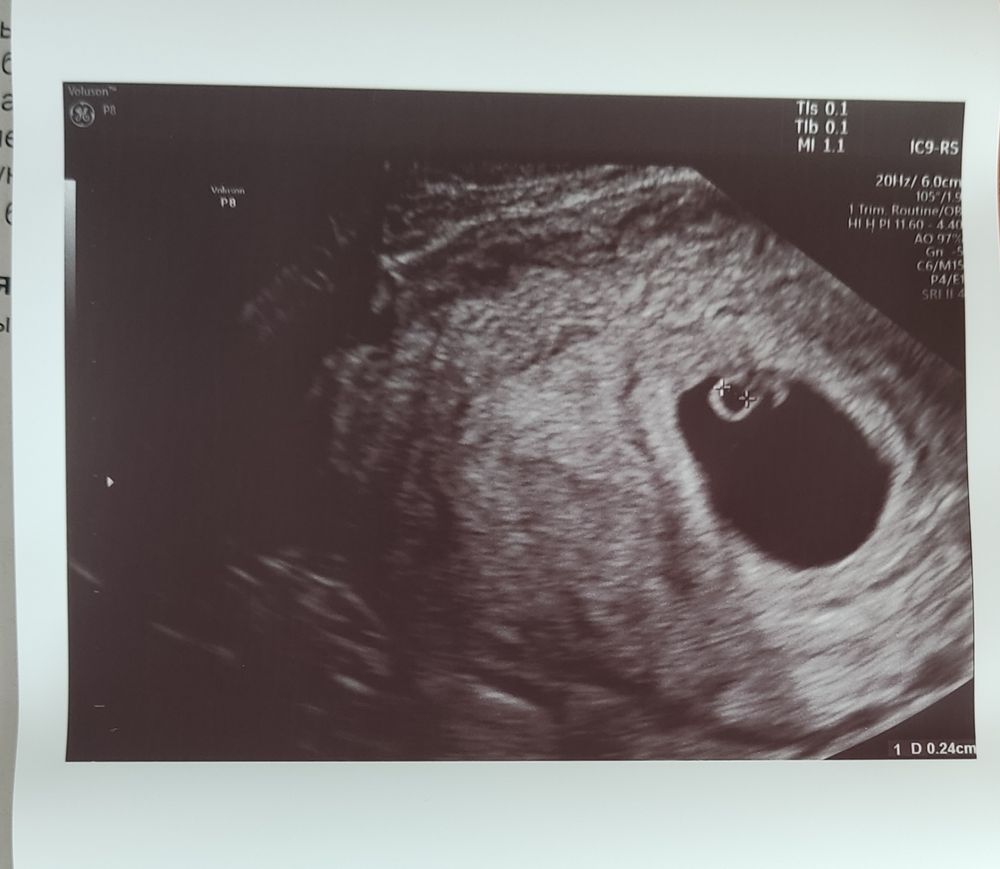

Срок по М: 5+6.

ПЯ - 18,8 ММ (6н+6д)

КТР - 5 ММ (6н+1д)

Сердцебиение ритмичное 💓 110 уд/в минуту.